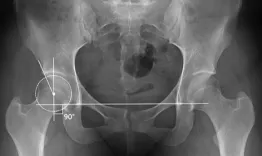

3 patients with borderline hips - conservative or recon?

The distinction between conservative surgery (PAO or arthroscopy) and non-conservative treatments has evolved significantly with the development of modern decision-making algorithms.

Live clinics: Hips- Indication limit. 3 patients with borderline hips- conservative or recon?

Nicolas Bonin, Kristoff Corten, Frédéric Laude, Nicolas Reina